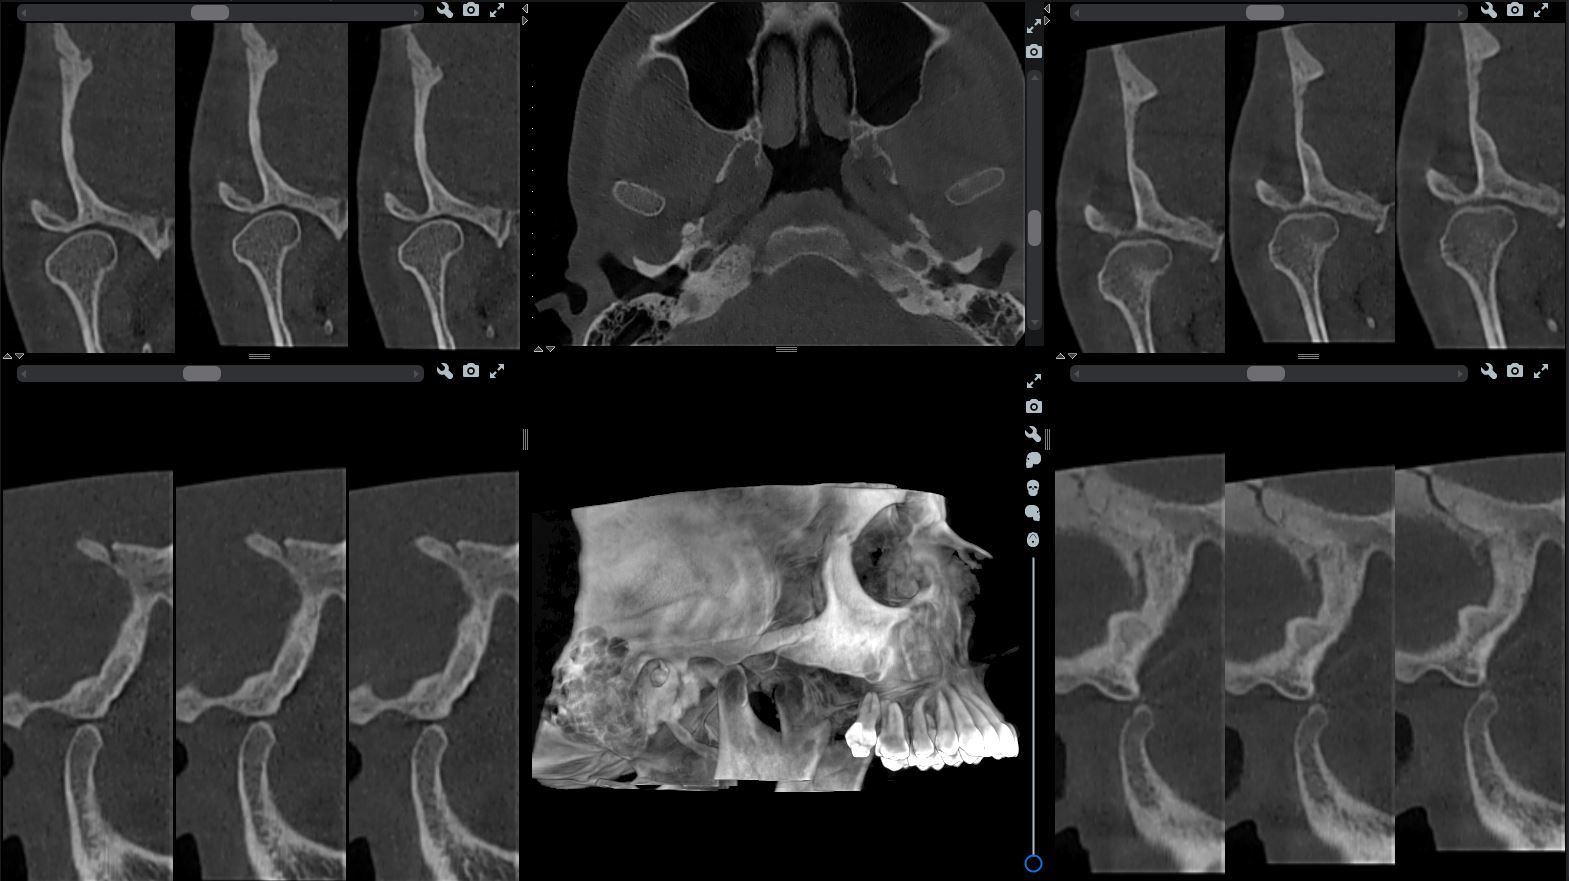

Визуализация височно-нижечелюстного сустава (ВНЧС)

Такие исследования нужны ортодонту и гнатологу (специалисту, занимающемуся реконструкцией зубных рядов, а также дисфункциями ВНЧС).